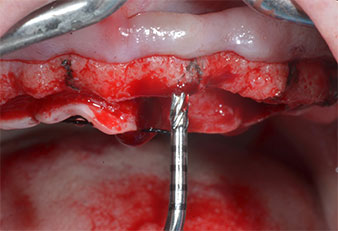

Debido al hueso relativamente duro (D2) existente en el sector anterior, los sitios de los implantes largos de 10 mm de las posiciones 11 y 21 se finalizaron con una fresa rotatoria de 4 mm de diámetro, en combinación con un contra-ángulo quirúrgico WS-75 L de W&H, el motor de implantes Implantmed de W&H y el módulo opcional Osstell ISQ de W&H. En cambio, debido a la existencia de hueso blando, los sitios posteriores se prepararon hasta un diámetro final de 3 mm utilizando el inserto Piezomed I3P. Por último, los implantes se colocaron a nivel crestal para su osteointegración durante tres meses (figuras 6-10). La prótesis existente se mantuvo sobre cuatro implantes provisionales (figura 8).